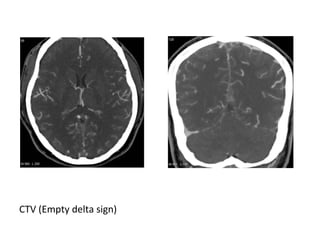

2-Empty Delta sign :

*The sign consists of a triangular area of enhancement

with a relatively low-attenuating center which is the

thrombosed sinus

*In early thrombosis the empty delta sign may be absent

and you will have to rely on non-visualization of the

thrombosed vein on the CECT

*The sign may be absent after two months due to

recanalization within the thrombus

CT+C : Empty delta sign due to thrombosis of the SSS

CTV (Empty delta sign)

CT+C (Empty delta sign)

CT+C ( Empty delta sign )